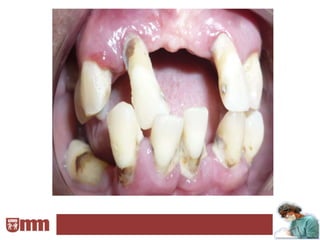

¿Cuándo esta indicada una P.P.R.?

1.- En individuos de edad avanzada o en jóvenes menores

de 20 años

2.- Cuando existen grandes espacios desdentados

3.- En caso de exhiba perdida ósea

4.- En extracciones recientes y en zonas extensas

desdentadas